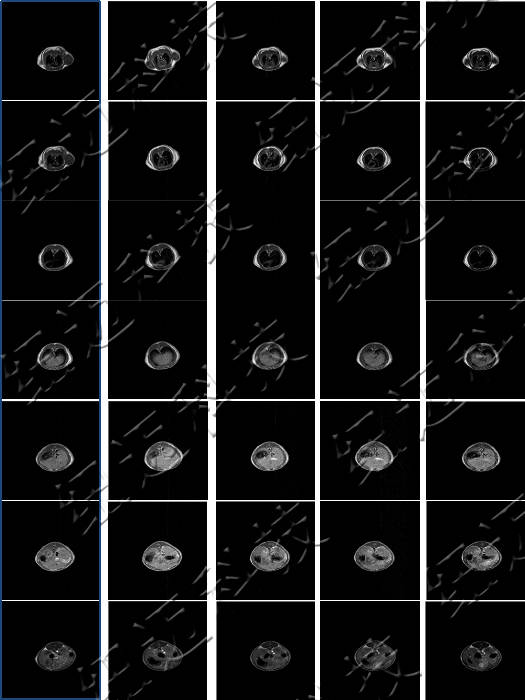

核磁共振成像(MRI)目前普遍應(yīng)用于醫(yī)學(xué)檢測(cè)成像中,具有無(wú)輻射損傷的安全性,可任意方位斷層掃描等技術(shù)靈活性,加以涵蓋質(zhì)子密度、弛豫、加權(quán)成像以及多參數(shù)特征的優(yōu)勢(shì),已成為當(dāng)代臨床診斷中最有力的檢測(cè)手段之一,然而臨床發(fā)現(xiàn)某些不同組織或腫瘤組織的弛豫時(shí)間相互重疊,導(dǎo)致診斷困難。